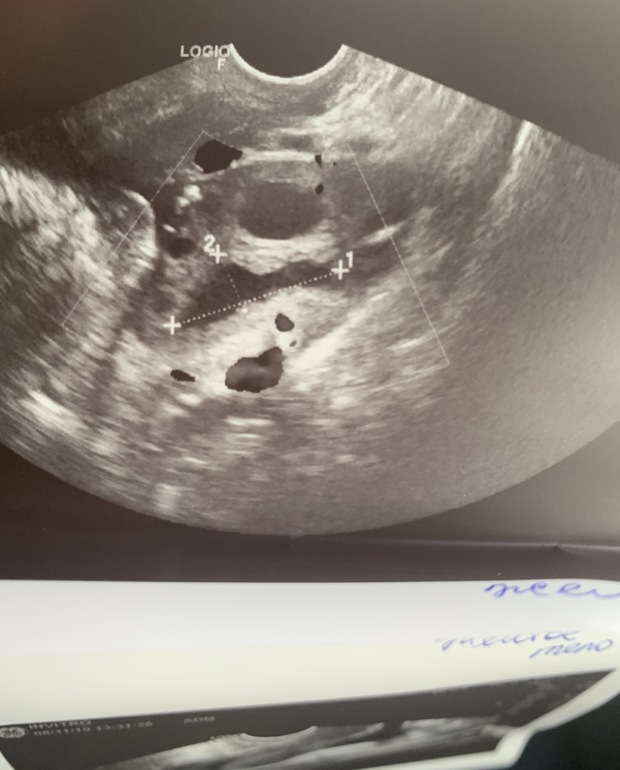

Вчера была на узи : в ЛЯ 2 ф 26 и 27мм

Видимо у меня также как у вас)была сегодня на узи, овуля была вчера или ночью, Как раз в день яркого теста, лопнули с интервалом, видимо, так как второе жт ещё не сформировалось до конца))сегодня уже полоска тусклее, как на 16дц вечером

Кстати, у меня точно также было тогда два ДФ и тоже оба лопнули, только с интервалом в несколько часов, т.к. второе жт ещё только формировалось) и тест был бледнее, а вечером совсем уже слабый.

В общем одно нормальное круглое , а второе вытянутое такое длинное, странным ей показалось, но сказала , что не сформировалось может ещё , только лопнул фоллик типа

Про сплющенное нет, просто написано, что неровные контуры с нечетким содержимым и ещн четотам) не помню)) но описание отличалось. У меня в обоих яйках по фоллику было. Врачи э ещё по разному описывают. На своём языке каждая)